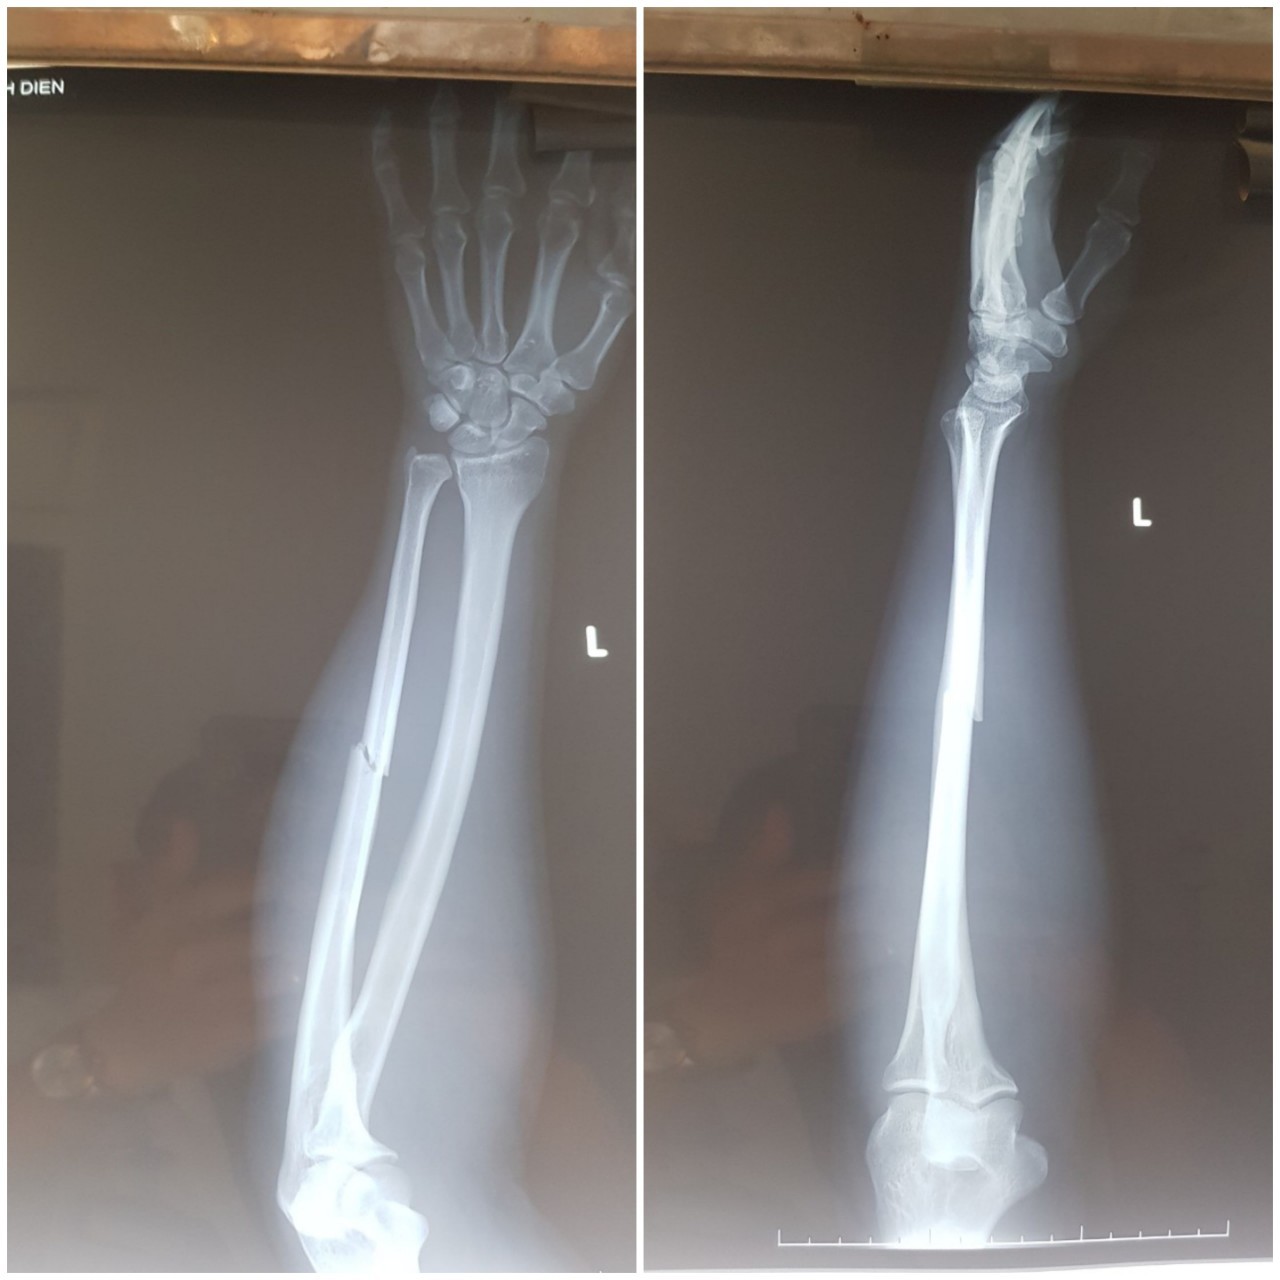

![]() |

| Tay trái của anh Điền và Khoa bị gãy do nhóm bảo vệ đánh. Ảnh: Anh Vũ |

Anh Điền và Khoa bị đánh gãy cánh tay, được đi cấp cứu.